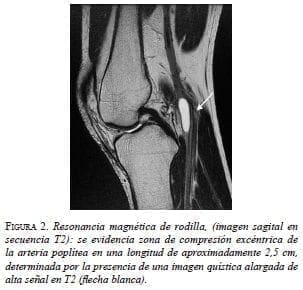

Con estos hallazgos, se planteó como primera posibilidad una enfermedad quística de la adventicia de la arteria poplítea, con estenosis crítica secundaria. Posteriormente, una resonancia magnética (RM) de rodilla demostró alteraciones similares (figura 2). En la angiografía por RM de la región poplítea se observó, además, la zona de compresión y ausencia de flujo segmentario en la arteria poplítea (figura 3).

Los quistes pueden ser vistos en la pared de la arteria poplítea, pero también en sus ramas, como las arterias geniculadas 8. Los quistes se observan hiperintensos en imágenes ponderadas en T2 (T2WI), mientras que, en imágenes ponderadas en T1 (T1WI), presentan intensidad de señal variable según las diferencias en su contenido mucoide 8,10. En los quistes de mayor tamaño se pueden observar tabiques en su interior 8. En secuencias contrastadas con gadolinio, no presentan realce o solo captación en anillo 10.

Tanto la angiografía por sustracción digital como la angio-RM pueden demostrar una estenosis concéntrica (en forma de reloj de arena) o excéntrica (signo de la cimitarra) 8, aunque también pueden ser normales o evidenciar oclusión arterial completa no específica 8.